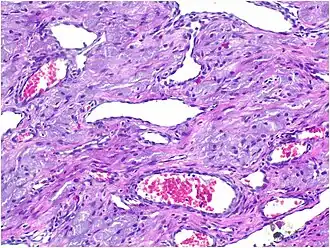

Histopathological Characteristics

Histopathologically, congenital epulis is usually characterized by the presence of big, rounded cells that fill the mucosa's lamina propria and have round to oval nuclei and an abundance of eosinophilic cytoplasm.[10] A thin layer of connective tissue separated the surface layer of cells from the growing new cells. Numerous histological traits, such as a fibrous and granulomatous appearance, have been reported in recent research.[10]

Microscopically, congenital epulis is composed of:

- Sheets of proliferating polygonal to round cells with overlying thin squamous, eosinophilic, granular cytoplasm[12][13]

- Centrally located, round nuclei [7]

These histopathological features are essential in distinguishing congenital epulis from other gingival and soft tissue neoplasms.